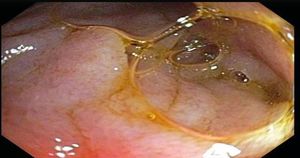

This gastrovascular disorder is rare yet life-threatening when it occurs. It is caused primarily by any process that leads to increased acuity of the aortomesenteric angle.